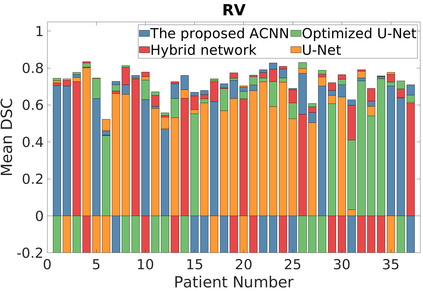

Deep Convolutional Neural Networks (DCNNs) are used extensively in biomedical image segmentation. However, current DCNNs usually use down sampling layers for increasing the receptive field and gaining abstract semantic information. These down sampling layers decrease the spatial dimension of feature maps, which can be detrimental to semantic image segmentation. Atrous convolution is an alternative for the down sampling layer. It increases the receptive field whilst maintains the spatial dimension of feature maps. In this paper, a method for effective atrous rate setting is proposed to achieve the largest and fully-covered receptive field with a minimum number of atrous convolutional layers. Furthermore, different atrous blocks, shortcut connections and normalization methods are explored to select the optimal network structure setting. These lead to a new and full-scale DCNN - Atrous Convolutional Neural Network (ACNN), which incorporates cascaded atrous II-blocks, residual learning and Fine Group Normalization (FGN). Application results of the proposed ACNN to Magnetic Resonance Imaging (MRI) and Computed Tomography (CT) image segmentation demonstrate that the proposed ACNN can achieve comparable segmentation Dice Similarity Coefficients (DSCs) to U-Net, optimized U-Net and hybrid network, but with significantly reduced trainable parameters due to the use of full-scale feature maps and therefore computationally is much more efficient for both the training and inference.